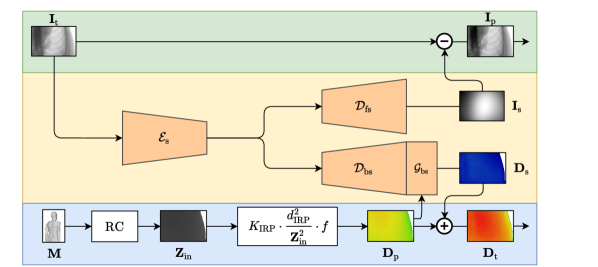

Figure 1 depicts the outline of the proposed method. The basic principle is to exploit our rich understanding of the photon interactions causing X-ray forward-scatter and back-scatter, respectively. Since both are caused by same underlying scattering interactions, it is reasonable to estimate their effects on image formation and skin dose together. Unfortunately, analytic and stochastic scatter estimation using established physics models is time-consuming and relies on accurate prior knowledge on the patient anatomy [3, 19, 29]. This can, however, be done faster and with a comparable accuracy, if we combine the underlying physics with a data-driven multi-task CNN. In particular, our approach involves KFP and a multi-task scattering model. Details are described below.

Especially the U-Net’s skip-connections lead to outputs covering the whole frequency spectrum. However, a Fourier analysis of Eqs. 2 and 3 for the diagnostic X-ray energy regime reveals mostly low-frequency characteristics. This observation is substantiated by the low amplitude and smoothness of the corresponding plots in Fig. 2. Therefore, we propose to degenerate the U-Net to a dual autoencoder-like CNN (DAE) without skip-connections to constrain its output frequency, as depicted in Fig. 1. While we keep the encoding path to extract the latent scatter distribution from , we split the decoding paths and to separately estimate and , respectively. Since forward- and back-scatter are based on the same particle interactions, it is reasonable for both to share the same latent space, while the decoders can be interpreted as opposing projections on either the detector (forward-scatter) or the patient skin surface (back-scatter). To further enforce low-frequency characteristics via a compact latent space, the number of feature maps is not doubled per down-sampling operation as it is typically done for the U-Net. Similar to , the encoder consists of six convolutional blocks (two layers with kernels and ReLU activations) with average pooling operations in between. The decoders resemble with bilinear up-sampling instead of average pooling. In addition, we extend by an additional convolutional block with as second input to account for the domain transfer to skin dose. The number of parameters to train is with k two magnitudes lower than the U-Net’s. In general, and have both different co-domains and SI units. To circumvent error-prone loss weighting, we used the mean absolute percentage error (MAPE) cost function.